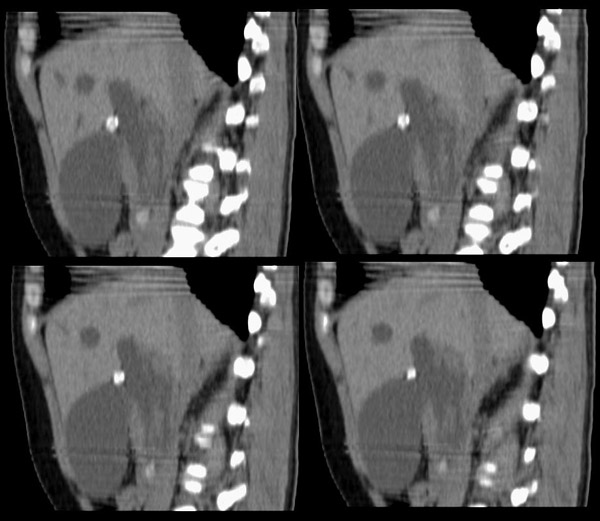

局部1mm薄层重建:

整个胆道系统内可见多发蛔虫钙化改变,胆道扩张.

行胆囊切除术及胆总管探查术:探查见肝脏大小正常,肝缘稍钝,肝表面光整,胆囊大小12*3*3cm3,壁水肿增厚约0。5cm,张力稍高,胆囊与大网膜呈纤维粘连;胆总管宽约2cm,壁明显增厚,触摸胆总管,隐约可触及一条状物,于胆总管做一长约1、5cm的纵行切口,用取石钳在胆总管内取出一条长约16cm长黑色的长条状物,较脆易折断,宽约0、6cm,证实为蛔虫尸体。用探子往下探,未发现下端结石最后诊断:胆道蛔虫症继发胆系梗阻性扩张。

疑惑:1、ct表现胆总管下端有结石影,但手术中未发现???